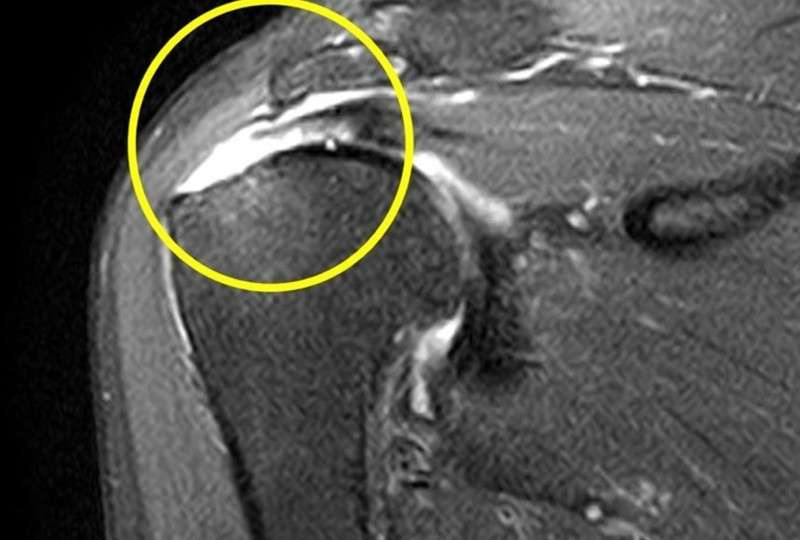

【MRI画像】

棘上筋の断裂を認める